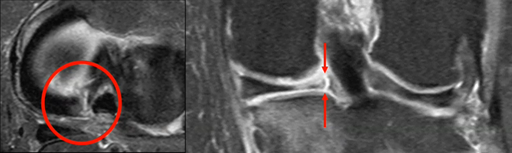

IRM des ligaments croisés

DEMONDION X. - CHRU LILLE

MAP 2014

Musculo-squelettique

IRM

Genou

Ligament

MAP

1 étapes